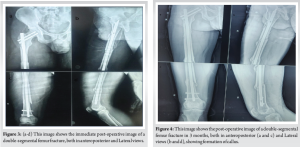

Post-operative course

Since Hb was 8.1 g/dL and HCT was 24.5%, the patient received an additional unit of packed RBCs on the 1st post-operative day and X-ray was done as shown in (Fig. 3). On the 2nd post-operative day, in-bed turning, active quadriceps, hamstrings, and ankle pump was initiated, and on the 5th post-operative day, he was allowed to touch down while bearing weight. Using a walker, partial weight-bearing was started on the 10th post-operative day. After being admitted to the hospital for 11 days, the patient was released. During his hospital stay, no other issues were observed. He was told to attend physiotherapy sessions after being released from the hospital, and several routine follow-up appointments were planned. Bone union was assessed using both radiological and clinical parameters throughout the follow-up period, after 3 months (Fig. 4) shows good callus formation. The knee range of motion after 90 days was adequate (full knee extension and up to 115° of flexion), and callus formation was noted at the 3-month follow-up visit. Ultimately, 120 days after surgery, he was able to bear his entire weight without help. The patient cautiously resumed his pre-fracture activities after radiological evaluations at the 6- and 9-month follow-up visits showed satisfactory fracture healing. During the 12-month follow-up period, the patient was completely content with the functionality of his limbs and was able to go about his everyday activities without experiencing any problems (Fig. 5 and 6).